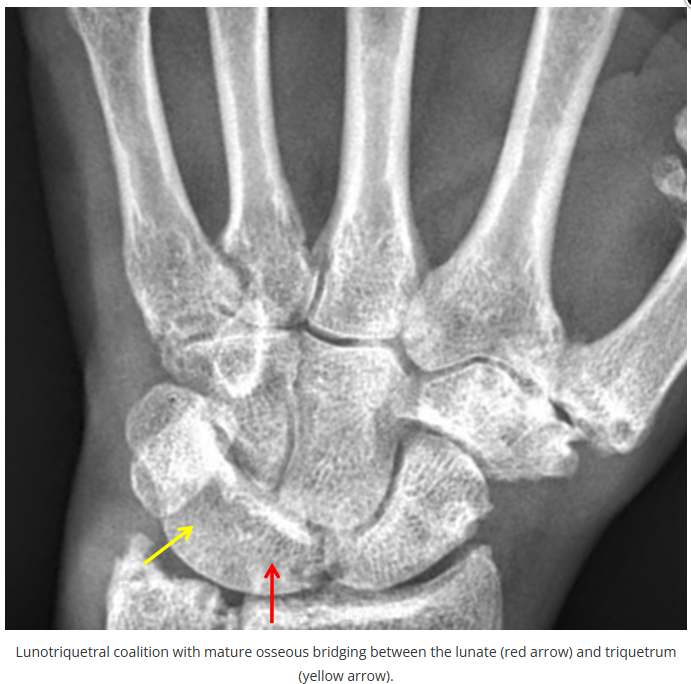

今天是腕部与手的X线片。所有X线片都

带有标注和说明

,可以选择长按图片,

自动翻译相关说明

。